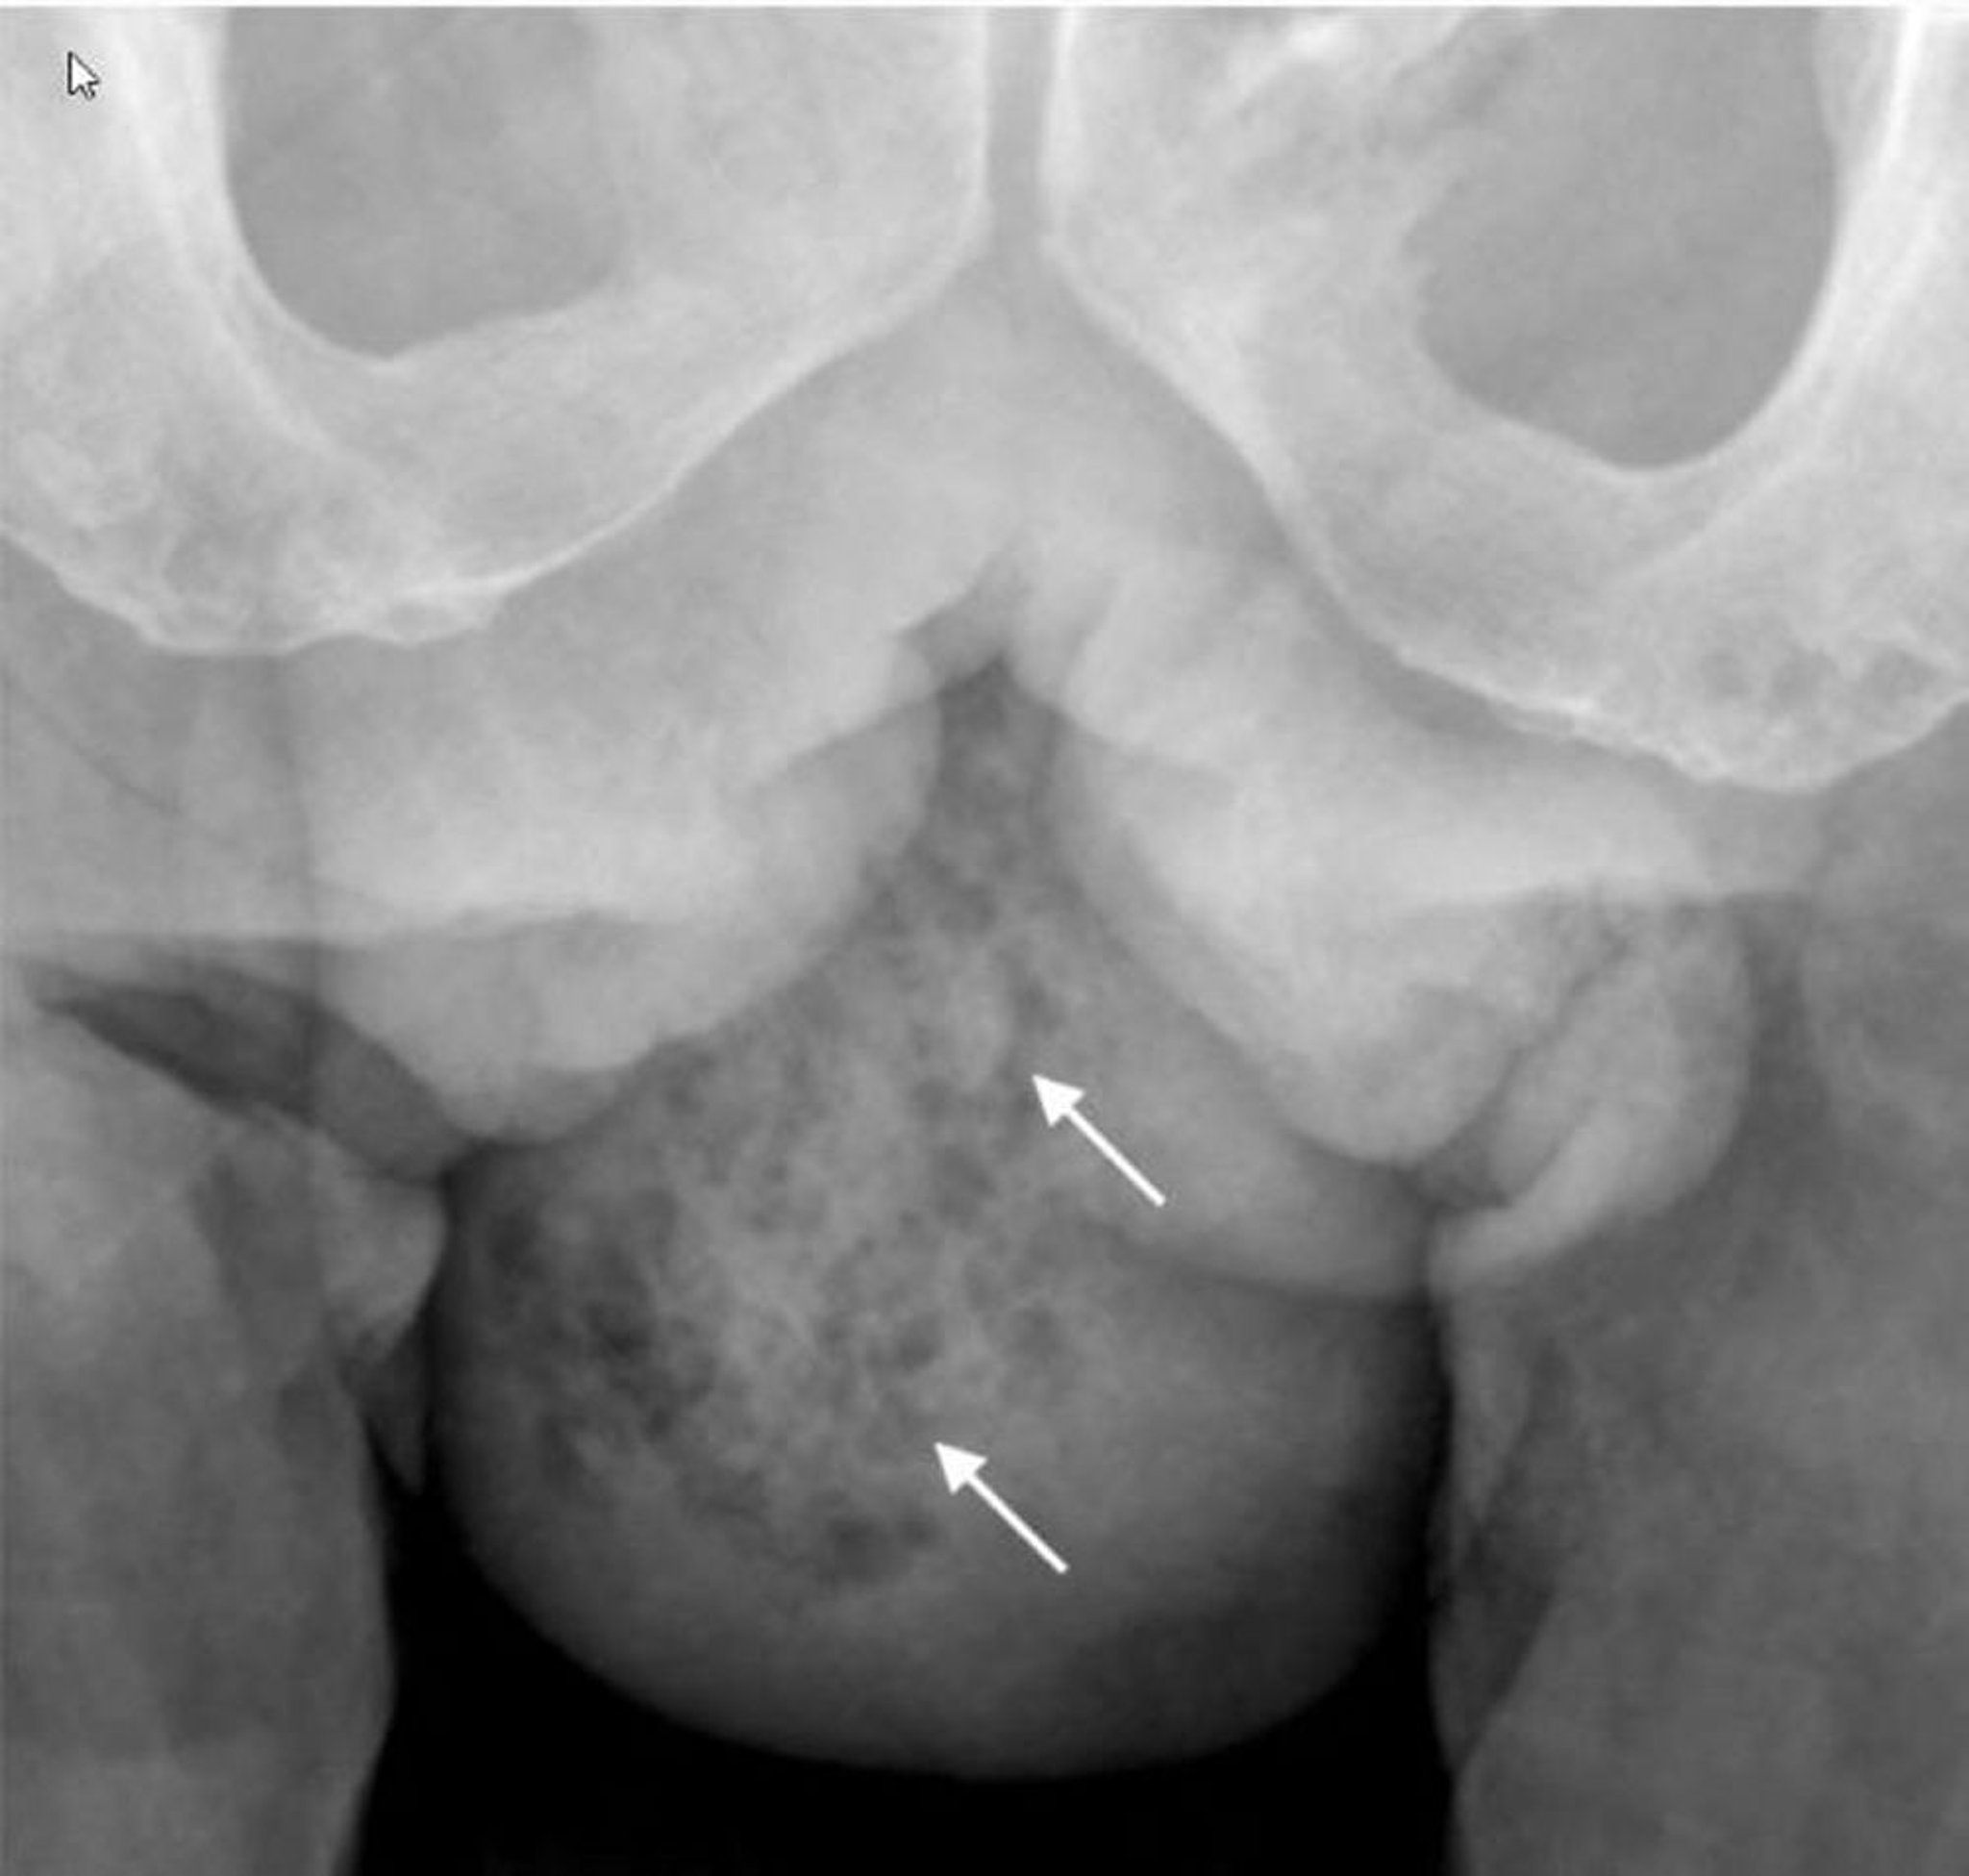

Fournier Gangrene (X-Ray)

This x-ray shows soft-tissue gas in the right hemiscrotum (arrows).